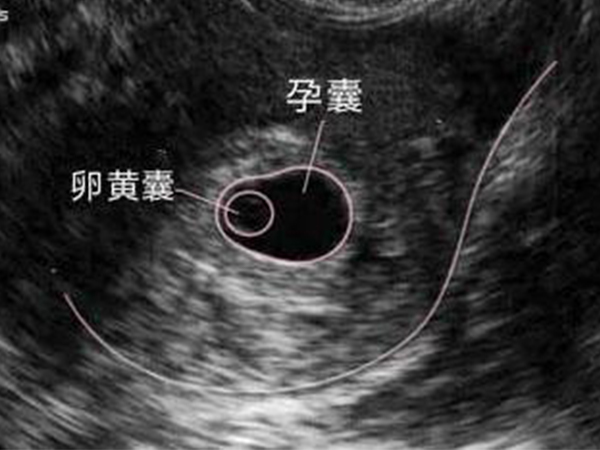

卵黄囊和孕囊的区别B超首次为你揭露其形状

卵黄囊是母体和胚胎交换的最初始途径,它位于孕囊里面,两者是有本质上的区别,而后随着孕周增加,卵黄囊的大小形状也不一样,在临床上通过B超检查,如果确定宫内有孕囊,..

卵黄囊和孕囊可不是一个意思,除了出现顺序还有这些区别

相信对于很多怀孕的妈妈来说孕囊和卵黄囊并不陌生,只是这二者的区别很多人都分不清,其实这二者都是胎儿发育的两种组织形式,通常孕囊比卵黄囊更早被发现,而卵黄囊位于孕..

卵黄囊和孕囊区别大,透过B超首次为你揭露其形状